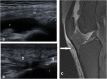

Methods and results: A prospective study was conducted on 143 patients with clinically confirmed AKP. All patients underwent ultrasonography and MRI examinations of the knee. The diagnostic accuracy of ultrasonography compared to MRI for evaluating different findings of possible causes of AKP were analyzed using receiver operating characteristic (ROC) curve and judged by area under curve (AUC). A total of 155 knees were included in the study; 26 knees showed no abnormalities, 19 knees showed positive MRI only, and 110 knees showed positive ultrasonography and MRI. Ultrasonography and MRI reported 11 different findings of possible causes of AKP or related to it. Joint effusion was the most common finding (38%) followed by trochlear cartilage defect (20.6%) and superficial infrapatellar subcutaneous edema (20%). The overall accuracy of ultrasonography was 85.3% sensitivity and 100% specificity. The ultrasonography provided the highest sensitivity (100%) in detecting bipartite patella, followed by 91.5% for joint effusion, and 87.5% for quadriceps tendinopathy. The ROC curve analysis of overall accuracy of ultrasonography showed an AUC of 0.93. The overall Kappa agreement between ultrasonography and MRI was good (k = 0.66).